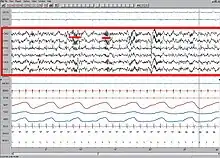

Le sommeil, tant sa régulation que son rôle, reste un mystère pendant des siècles. Le développement de l'électroencéphalogramme (EEG) au XXe siècle permet son étude.

Un de ses assistants, Eugene Aserinsky, remarque sur l'électroencéphalogramme des oscillations de grande amplitude, correspondant à des mouvements oculaires, un relâchement du tonus musculaire de la nuque (chez l'être humain qui peut relâcher volontairement ces muscles et ceux du menton), suivi d'une intense activité du cortex cérébral lorsque les sujets amorçaient le quatrième stade. La présence de mouvements oculaires rapides ou MOR (REM, Rapid eye movements en anglais) permet d'assimiler cette phase aux rêves : elle fut alors baptisée « sommeil rapide » ou « paradoxal » en 1961 par le Français Michel Jouvet, alors chercheur au CNRS à Lyon.

Les données de l'EEG pendant la veille et le sommeil sont communes à tous les mammifères. Par contre, il semblerait qu'il y ait quelques différences chez les mammifères primitifs comme l'échidné. Ces données permettent de distinguer différents stades dans le sommeil.

Sur l'EEG, l'activité néocorticale est plus proche de celle de l'éveil que celle du sommeil lent, c'est là le « paradoxe ». La respiration est irrégulière. Le cœur accélère ou ralentit. Chez l'être humain, on observe une dilatation des organes pelviens et une érection qui peut être suivie d'éjaculation. Cette phase se répète toutes les 90 minutes environ, et sa durée s'allonge avec la succession des cycles du sommeil, pour devenir maximale en fin de nuit. C'est la période propice aux rêves, bien que les rêves puissent survenir pendant le sommeil lent.

Le sommeil paradoxal correspond environ à 20-25 % du temps total de sommeil. Le souvenir des rêves a longtemps été associé avec la présence de sommeil paradoxal. En réalité, on pense aujourd'hui que nous pourrions rêver au cours d'autres stades[79]. Cela dit, les enregistrements polygraphiques (EEG, EMG et EOG) ont permis de montrer une certaine corrélation entre le rêve et le sommeil paradoxal. Des études ont été faites en réveillant plusieurs individus à différents stades du sommeil. Elles ont montré que la qualité du souvenir qu'ils gardent de leur rêve est fonction du stade auquel ils sont réveillés.